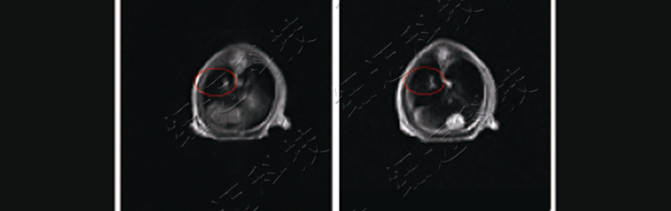

3、造影剂在裸鼠体内(肿瘤)作用评价

4、裸鼠肺部原位肿瘤位置排查